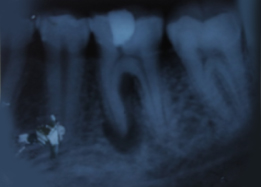

Hemisectomy

Immediate Post-Surgical IOPAR